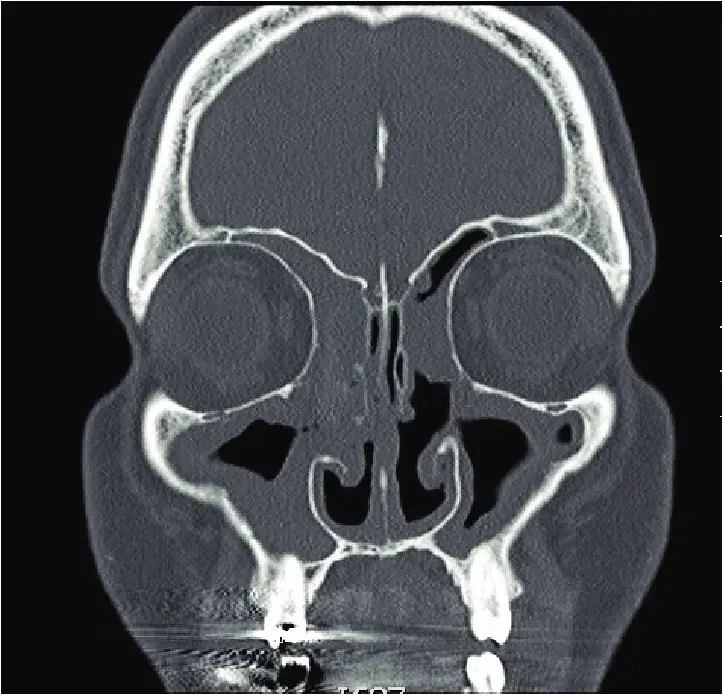

I polipi sono formazioni benigne che crescono all’interno delle cavità nasali e dei seni paranasali.

Possono causare:

naso chiuso persistente

perdita dell’olfatto

secrezioni nasali

sinusiti ricorrenti

In alcuni casi possono essere associati ad asma o allergie.

Sinusite cronica

La sinusite cronica è un’infiammazione persistente dei seni paranasali.

valutazione dei seni paranasali